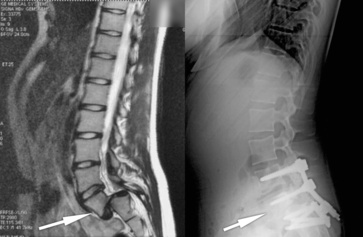

Chirurgien expérimenté

Le cabinet médical est spécialisé dans la chirurgie du rachis depuis 1985. Le Docteur Chiffolot réalise plus de 2500 consultations du dos et plus 520 interventions par an du rachis entier (hernie discale, arthrodèse lombaire…).